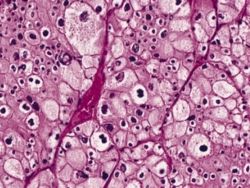

A renal cell carcinoma (chromophobe type) viewed on a hematoxylin & eosin stained slide